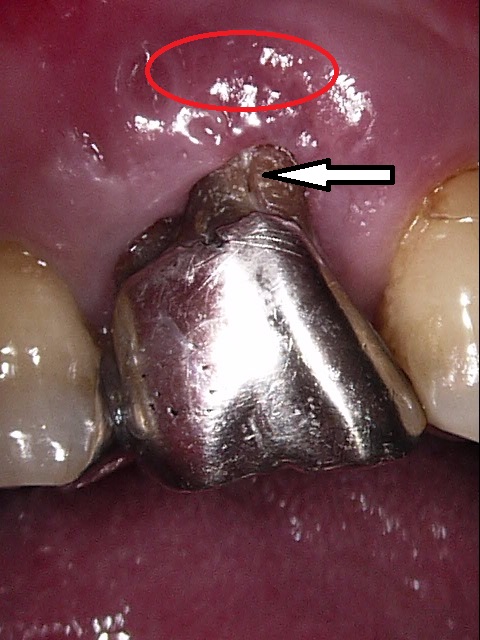

赤丸の部分の歯ぐきが腫れています。矢印の部分は歯の縦に亀裂が入った様子が見られます。

金属のメタルコアを除去して、ファイバーポストに置き換え、歯根破折のリスクを軽減したケース↓ 3本の歯にそれぞれメタルコアが入っています。

メタルコアを除去しました↓

代わりにファイバーポストを入れて、レジンコアで補強しました。

患者さんにブリッジとインプラントのメリット・デメリットをお話ししたところ、今回はブリッジを選択されましたので、ブリッジによる歯根破折のリスクを少しでも下げるために、すべての歯のメタルコアをファイバーポストに置換しました。